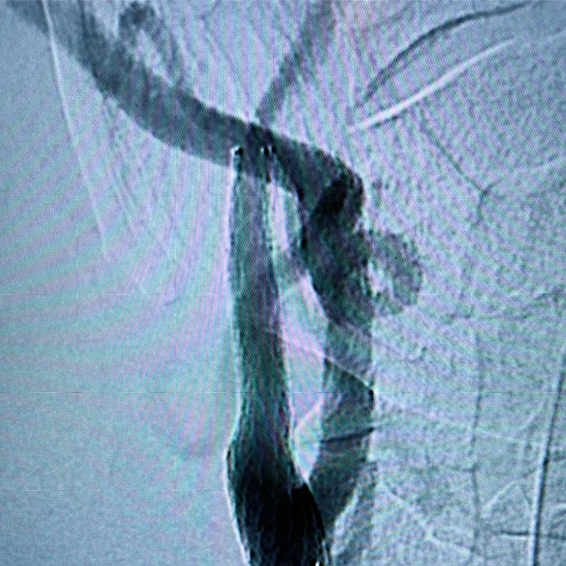

Desobstrução de Artérias Carótidas